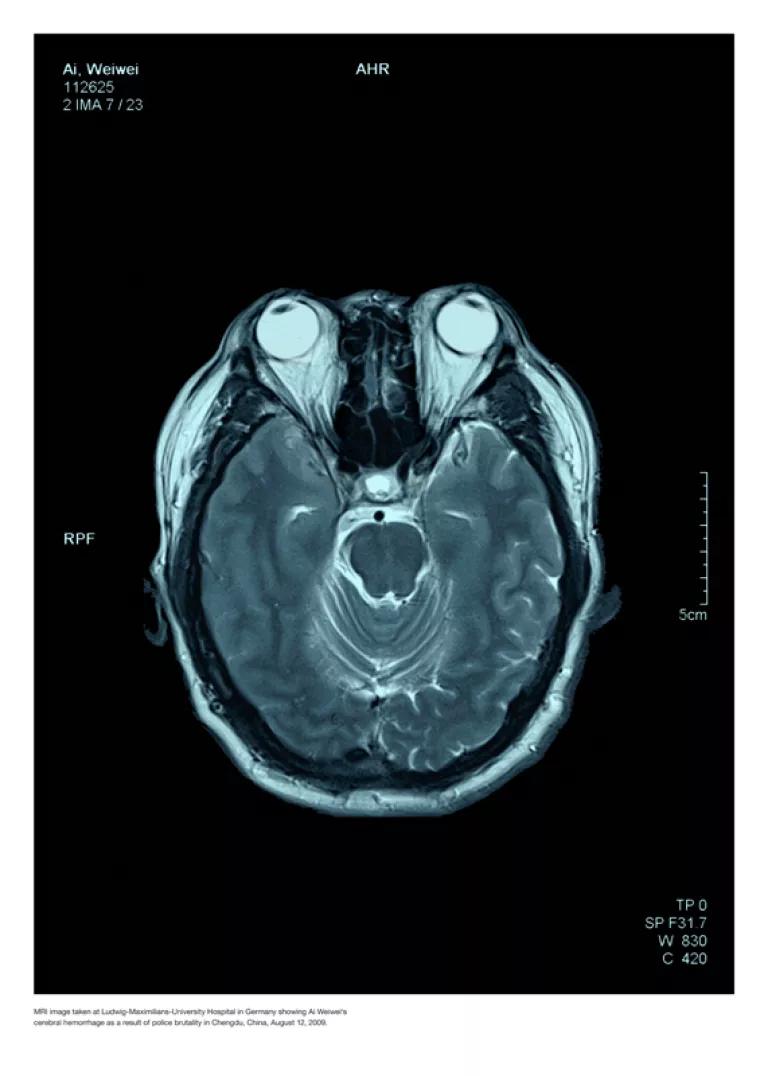

Ai Weiwei – Police Brutality, 2010/2011

Digitaler 11-Farben Pigment-Print einer Computertomographie auf Fabriano Designo Satinato, 50 % Cotton 300 g

Ai Weiwei geb. 1957 in Peking. Der Künstler und Kurator ist Sohn des Dichters Ai Qing. Er studierte an der Filmakademie Peking und ab 1981 an der Parsons The New School for Design in New York. 1993 kehrte er nach Peking zurück, entwarf sich ein Wohnatelier und begann, auch als Architekt zu arbeiten. Teilnahmen an der 48. Biennale Venedig und der documenta XII, weltweite Einzelausstellungen. Mit Jacques Herzog und Pierre de Meuron entwickelte er das Konzept für den „Vogelnest“-Bau des Pekinger Olympiastadions. 2009 wurde er von Polizisten zusammengeschlagen, damit er nicht als Zeuge in einer gerichtlichen Ermittlung zu Pfusch am Bau bei Schulgebäuden aussagen konnte; diese waren bei einem Erdbeben eingestürzt und hatten Tausende von Kindern unter sich begraben. Im September 2009 zeigten sich die Spätfolgen; während eines Aufenthalts in München mußte Ai wegen eines Hämatoms im Gehirn notoperiert werden. Von April bis Juni 2011 war er inhaftiert.